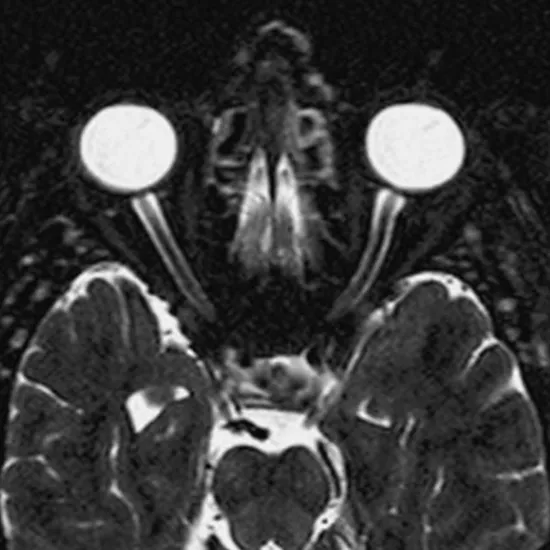

MRI scans of the orbits measure the size of masses inside or behind the globe. MRI orbit scans are used to find out if there is a mass inside or behind the eye, a complicated infection, optic neuritis, another cause of vision loss, or thyroid ophthalmopathy. The 3D image clarifies if there is a problem or disease in the eye.

Orbit MRI scans are used to find tumors, infections, and long-term diseases that affect the structures in and around the orbits. Also, it detects if someone has Grave's disease.

MRI Eye is a Magnetic Resonance Imaging non-invasive medical diagnostic tool used to diagnose abnormalities in and around the eye. MRI Eye is used to show abnormalities in the eye like infections in the eye, masses in the eye, vision abnormalities, optic nerves etc.